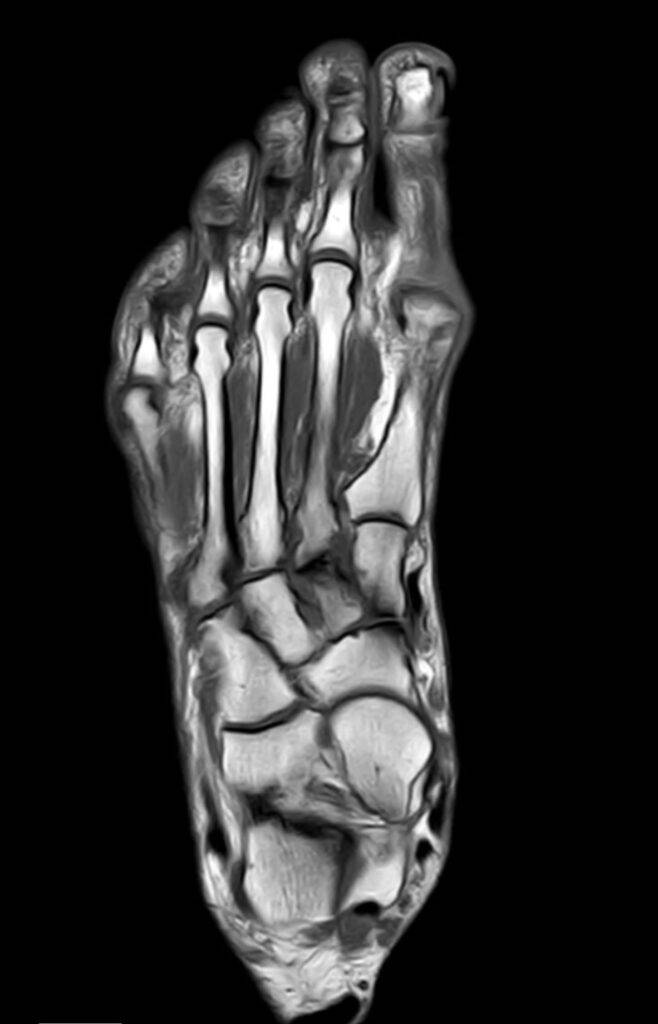

- Knochen: Knochenstrukturen, sowie das Sprunggelenk selbst werden in der MRT detailliert dargestellt. Die Unterschenkelknochen (Tibia und Fibula) sind ebenfalls sichtbar.

Wie sieht die Fuß Anatomie des Sprunggelenks aus?

Das Sprunggelenk ist eine komplexe Struktur, die aus verschiedenen Knochen, Gelenken, Bändern, Sehnen und Muskeln besteht.

| Knochen | Schienbein, Wadenbein, Sprungbein |

| Gelenke | oberes und unteres Sprunggelenk |

| Bänder | mediales und laterales Band, Syndesmose |

| Sehne | Achillessehne, Peronealsehne |

| Muskeln | Wadenmuskulatur |